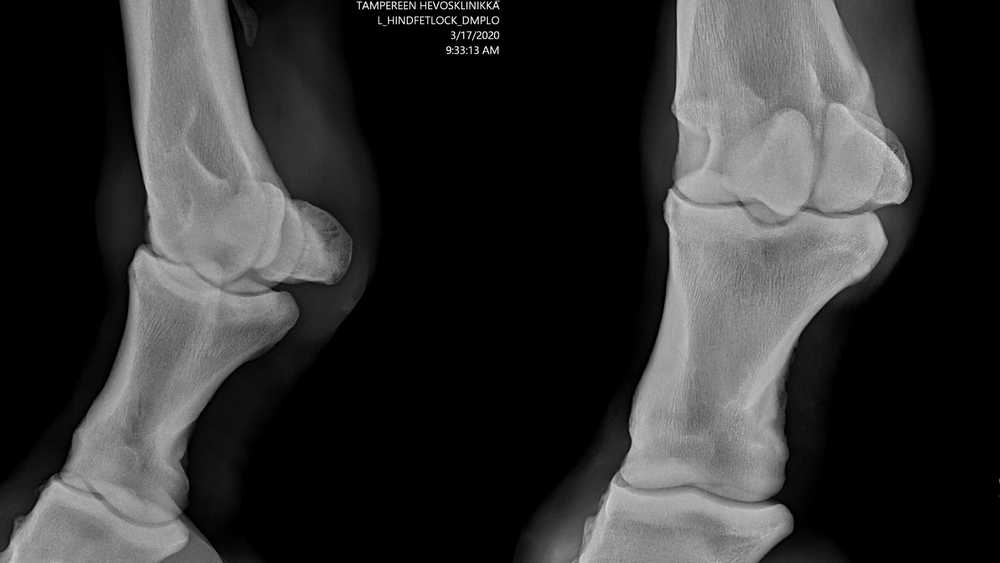

Onneksi Tampereen hevosklinikka tekee nykyään myös kotikäyntejä ja vuohinen saatiin maaliskuussa röntgenkuvattua kotitallilla.

Homma oli paketissa reilussa tunnissa, Sotilaan kanssa rauhoittavia ei tarvittu ja viidelle röntgenkuvalle, taivutustutkimukselle ja vuohisen piikitykselle kortisonilla tuli hintaa kotikäyntimaksuineen vain pari sataa. Teivon klinikka on ollut ahkerassa käytössä aiemminkin eikä asiakaspalvelu ole koskaan tuottanut pettymystä.

Röntgenkuvissa näkyy alkavia nivelrikkomuutoksia. Löydökset ovat melko tavallisia 16-vuotiaalle kilpauran tehneelle hevoselle, mutta ovat kuitenkin niin lieviä, etteivät röntgenkuvat tarjonneet helppoa selitystä sitkeälle tulehdukselle. Nivel piikitettiin toistamiseen kortisonilla ja eläinlääkäri antoi arvioin, että mikäli nivel ei vastaa hoitoon, on ennuste urheilukäyttöön huono.